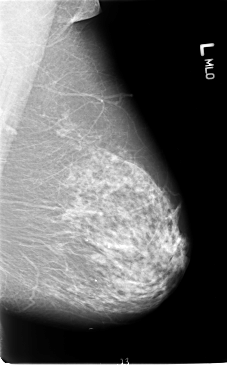

B_3057_1.LEFT_MLO

LEFT_MLO LINES 5840 PIXELS_PER_LINE 3624 BITS_PER_PIXEL 12 RESOLUTION 50 NON_OVERLAY